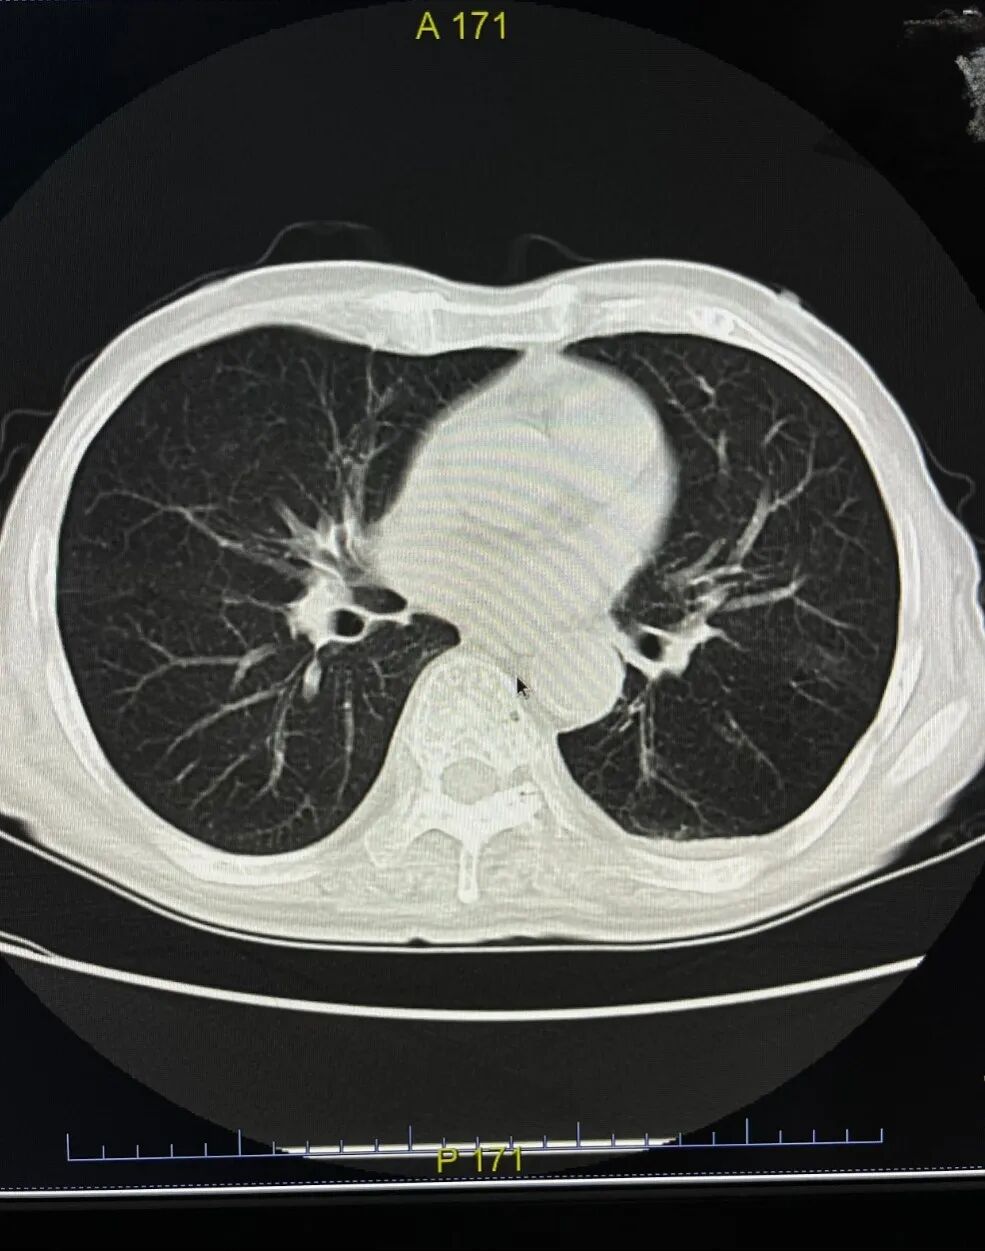

△分院患者检查申请单+胸部CT

在2022年成立了医学远程心电诊断会诊中心、影像诊断中心,初步实现“分院检查,总院诊断,医共体内互认”的目标。2024年正式落实医共体内大型医疗设备(CT/MRI/胃肠镜检查)共享机制,操作流程:医共体分院医生在分院开具大型医疗设备检查申请单,患者在分院缴费后,通过绿色通道,到总院优先安排进行辅助检查。患者只需支付一级医疗机构的检查费用就可以享受到二级医院的专业检查。分院医生可通过医共体总院系统专线查看相应检查结果,有效提高了各分院的服务质量。医共体内大型医疗设备共享解决了基层分院检查难、诊断难的问题,改善了人民群众的就医感受。